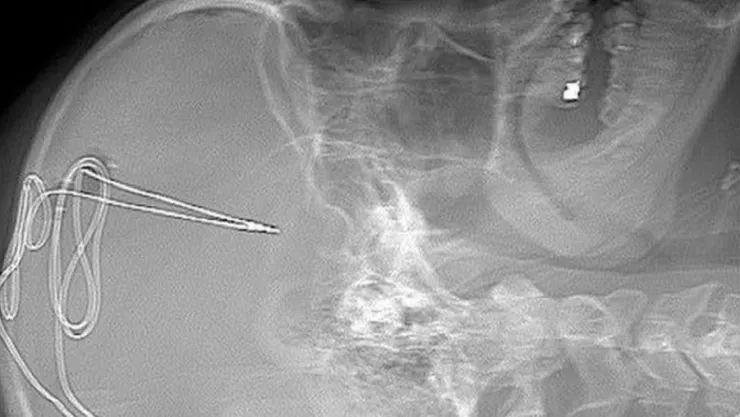

A los cuatro voluntarios se les insertó un electrodo de un milímetro en un área específica del cerebro que se encarga de regular los impulsos. Para monitorear la actividad cerebral se les colocó una batería debajo de la clavícula para observar si la ansiedad y deseo de consumir drogas logra disminuir.

Esta medida se le conoce como estimulación cerebral profunda (DBS) y está aprobada tanto por ellos como por la Administración de Alimentos y Medicamentos (FDA), siendo esta la primera vez que se utiliza en el combate a la adicción a las drogas en Estados Unidos; los pacientes serán monitoreados por los próximos dos años.